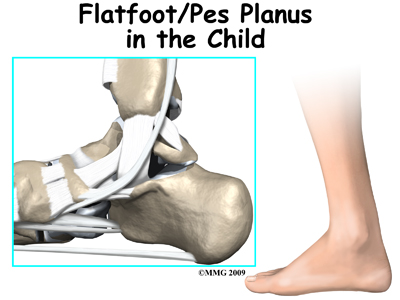

Flatfeet (also known as pes planus) describes a condition in which the longitudinal (lengthwise) and/or medial (crosswise) arches of the foot are dropped down or flat. The entire bottom of the bare foot is in contact with the floor or ground surface during standing, walking, and other weight bearing activities. Congenital means that the condition is present at birth in one or both feet. When only one foot is affected, the problem is referred to as unilateral pes planus or flatfoot. When both feet are involved, the condition is bilateral flatfeet. Sometimes the term ‘fallen arch’ is used, but doctors prefer not to use this term in favor of the more accurate medical term ‘pes planus.’

The anatomy of the foot is very complex. When everything works together, the foot functions correctly. When one part becomes damaged, it can affect every other part of the foot and lead to problems. With a flatfoot deformity, bones, ligaments, and muscles of the foot are all affected. Areas up the biomechanical chain such as the ankle, the shin, the knee, the hip and the low back can also be affected due to the misalignment that occurs.